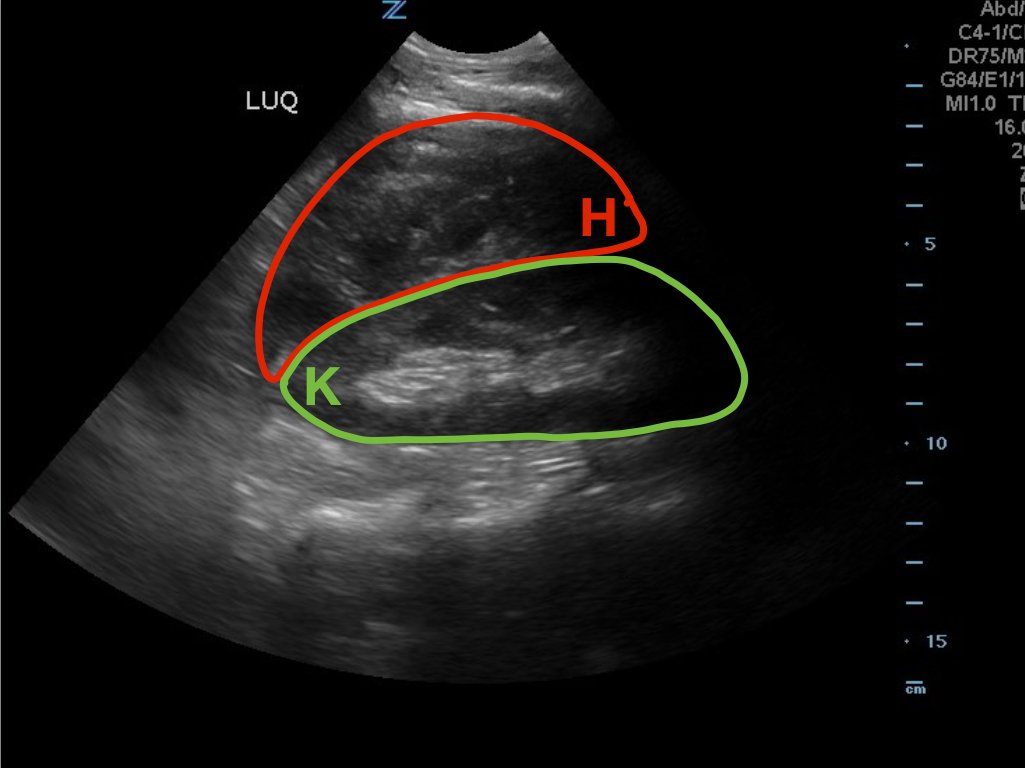

A 49-year-old male presents for evaluation of hematuria and left flank pain after mechanical fall down stairs four days ago. Point-of-care ultrasound (POCUS) focused assessment with sonography in trauma (FAST) exam demonstrated subcapsular renal hematoma. Once a subcapsular hematoma is recognized the provider should keep in mind that this condition may be managed conservatively in patients with two normally functioning kidneys, but may require urgent intervention if the patient is at risk for significant renal disease, such as a single kidney. The use of bedside ultrasound can expedite diagnosis and care for these patients, and allow proper consultants to be contacted early. Some consultants that may need to be consulted include nephrology, urology, and/or internal medicine. This case report emphasizes the utility of the FAST exam for patients presenting for non-acute trauma. The FAST exam can be utilized not only to identify free fluid in the abdomen and pelvis but also to visualize organs and the surrounding tissues for abnormalities after a trauma.